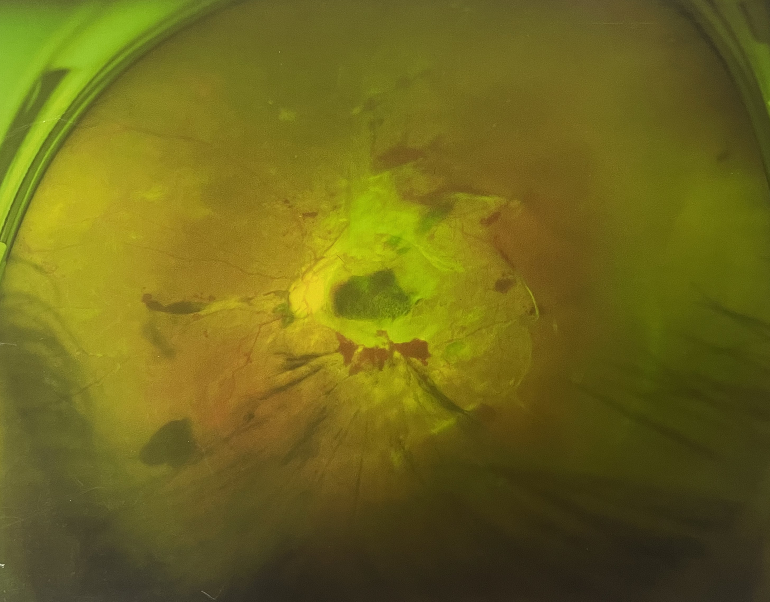

【文章導(dǎo)讀】眼底出血一般多久能好?眼底出血可以由眼科本身疾病引起,常見(jiàn)的是視網(wǎng)膜靜脈阻塞、糖尿病視網(wǎng)膜病變、中心性滲出性視網(wǎng)膜病變、視網(wǎng)膜動(dòng)脈硬化、老年性黃斑病變、視網(wǎng)膜靜脈

眼底出血一般多久能好?眼底出血可以由眼科本身疾病引起,常見(jiàn)的是視網(wǎng)膜靜脈阻塞、糖尿病視網(wǎng)膜病變、中心性滲出性視網(wǎng)膜病變、視網(wǎng)膜動(dòng)脈硬化、老年性黃斑病變、視網(wǎng)膜靜脈周?chē)住?/div>

另外,眼底出血還可以由全身疾病引起,比如糖尿病可以引起眼底出血,高血壓也會(huì)引起眼底出血,還有嚴(yán)重的腎病,血液方面的疾病都可以導(dǎo)致眼底出血。

眼底出血一般多久能好?眼底出血會(huì)影響患者視力,視物模糊,一定要重視眼底出血,早發(fā)現(xiàn)、早治療,這樣治療效果才能更好,患者生活質(zhì)量才能有所提高。

眼底出血一般多久能好?眼底出血如果是輕癥,時(shí)間較短的患者大約3-6個(gè)月可以恢復(fù),如果是重癥或者病程較長(zhǎng)的患者,可能要持續(xù)1年,甚至2年時(shí)間。

眼底出血一般多久能好?眼底出血在眼科比較常見(jiàn),治療相對(duì)比較復(fù)雜。因其會(huì)影響患者視力,可能會(huì)因此而失明。

眼底出血一般多久能好?眼底出血是醫(yī)生用檢眼鏡才能看到,患者和其他人看不見(jiàn)。眼底出血不是單獨(dú)的病,一般來(lái)說(shuō)是由眼科本身疾病造成,還可以由全身疾病造成。比如常見(jiàn)的視網(wǎng)膜靜脈阻塞、糖尿病視網(wǎng)膜病變等引起的眼底出血較常見(jiàn)。眼底出血一般多久能好?所以眼底出血的出血吸收時(shí)間也不一樣,要根據(jù)病情輕重決定其預(yù)后,出血吸收時(shí)間也不一樣。